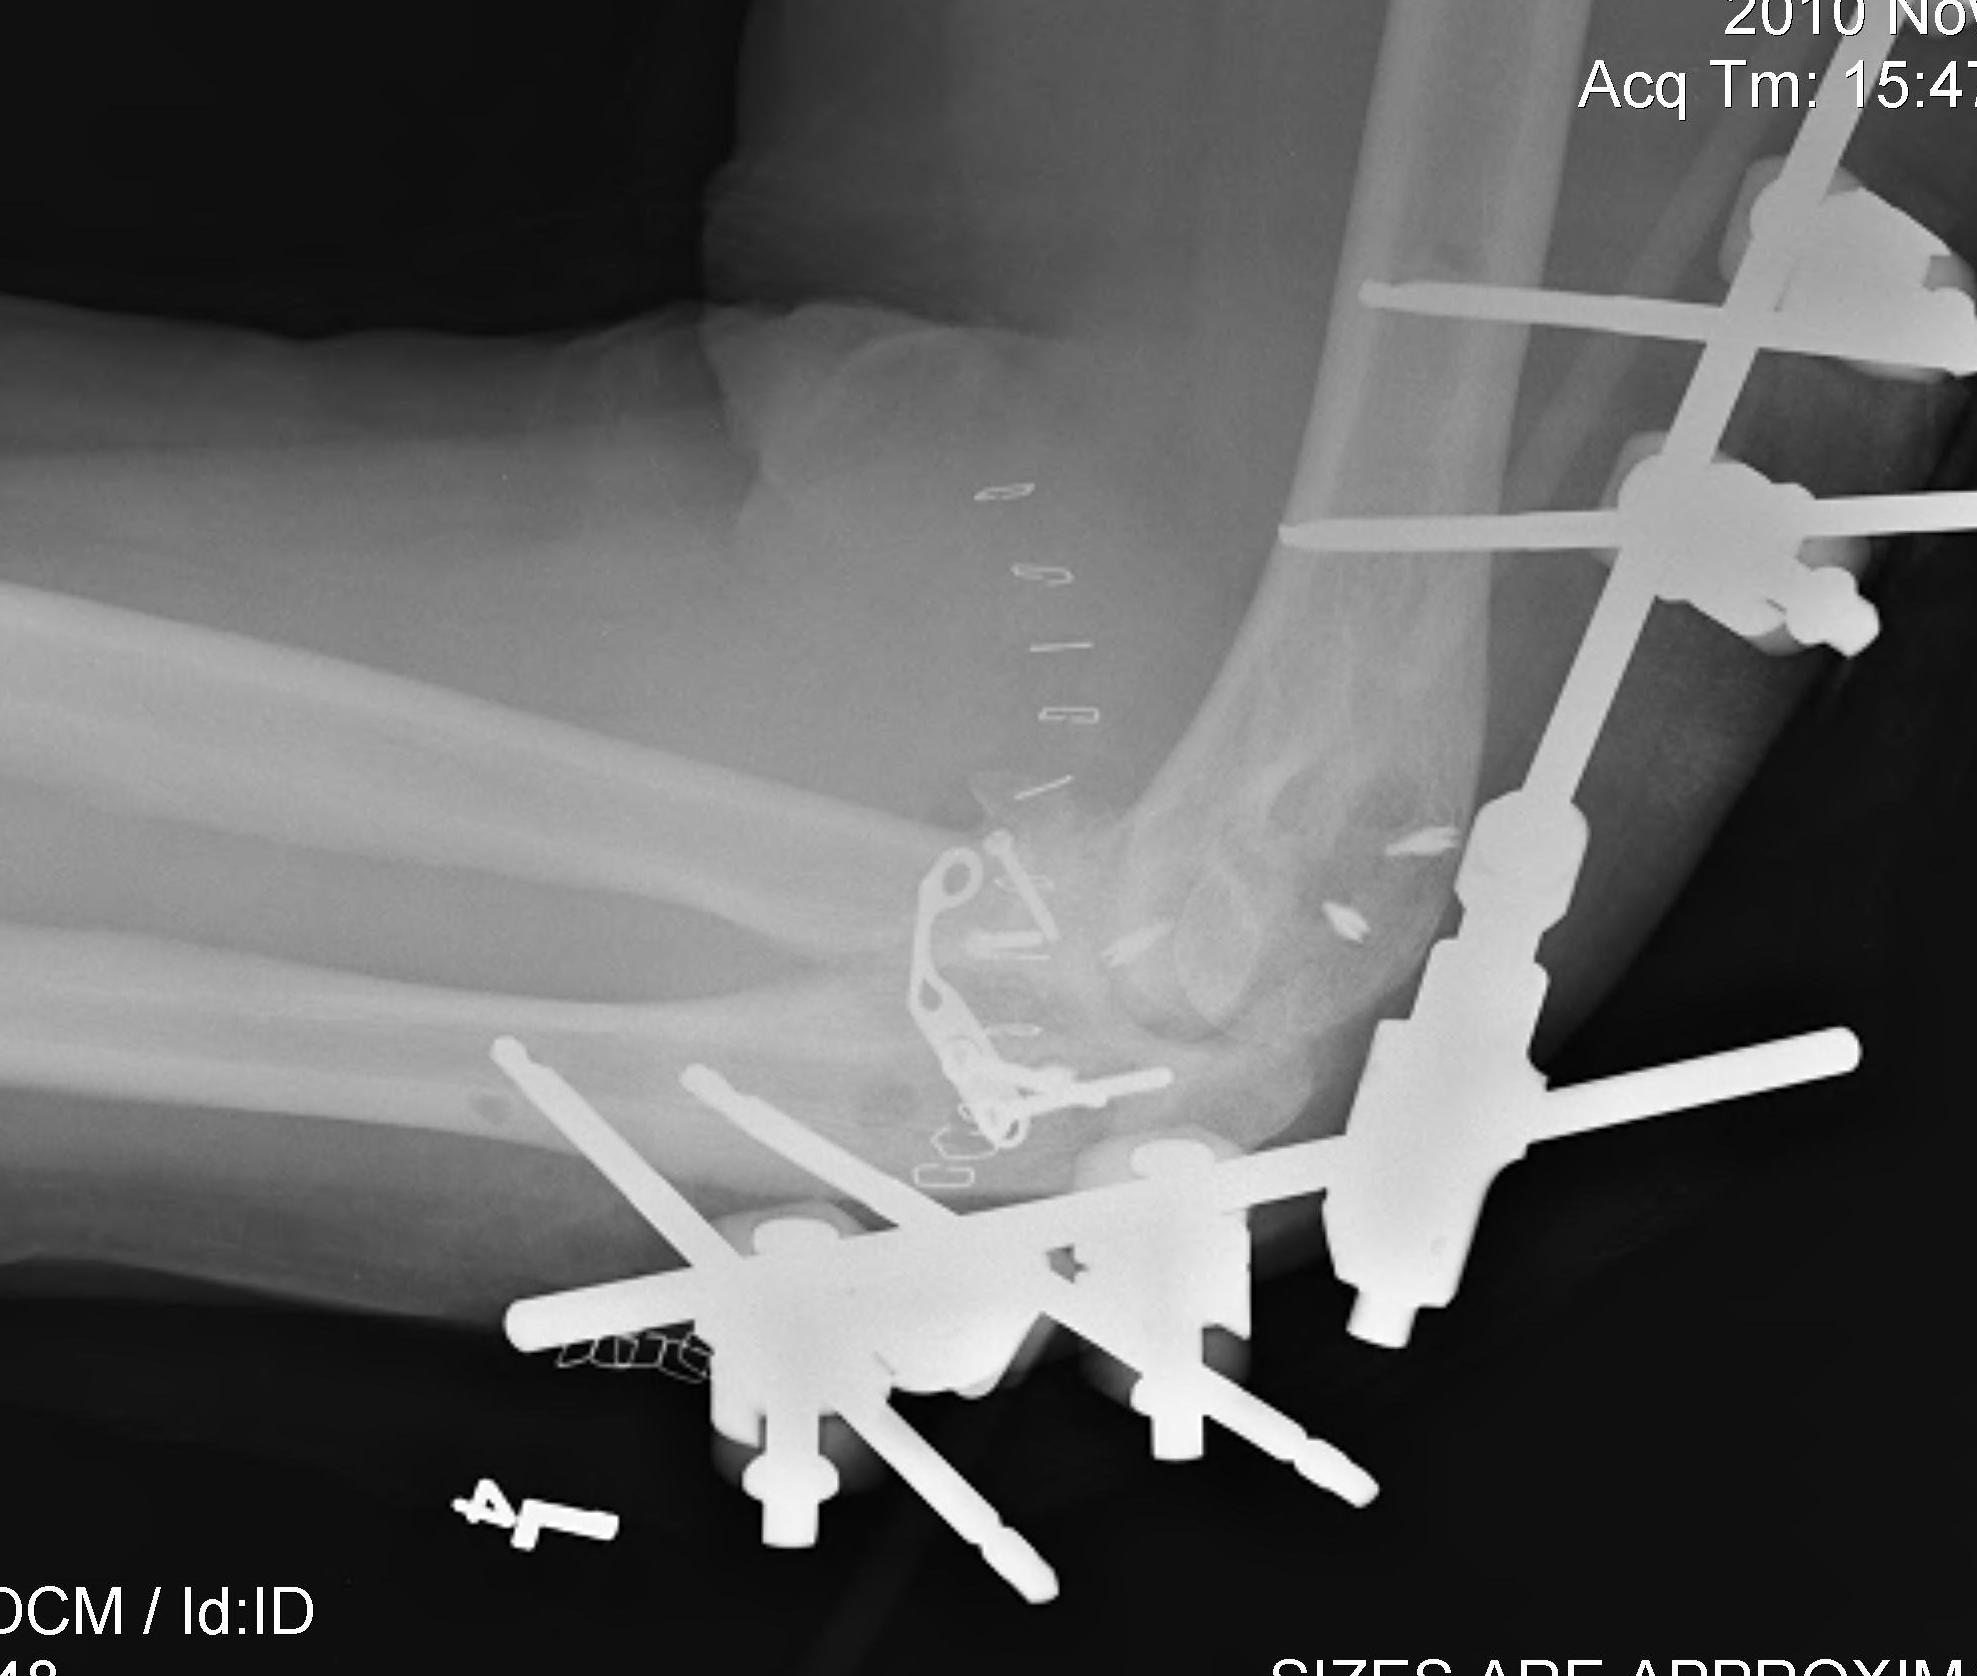

Technique

Depends on site of ectopic bone

AO foundation surgical release of elbow HO

Universal posterior approach

Lateral approach

- Kaplan approach - interval between ECRB and EDC

- anterior capsulectomy

- elevate triceps and aconeus posteriorly

- posterior capsulectomy

Medial approach

- ulna nerve release

- over the top approach - elevate anterior half of flexor pronator mass

- posteriorly elevate triceps

+/- hinged external fixator